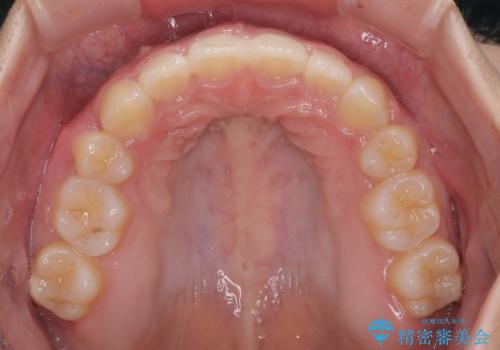

- 上顎前歯が飛び出していて唇がうまく閉じられないとのことで来院された患者様です。

くちばしのように前歯が突出していたため、口元を積極的に引っ込めるために、上下左右の小臼歯4本を抜歯することとしました。

また、上顎歯列が下顎に対して前方位に位置していたため、補助装置を用いて上顎歯列を後方に移動させ、より積極的に口元を下げるようにしました。